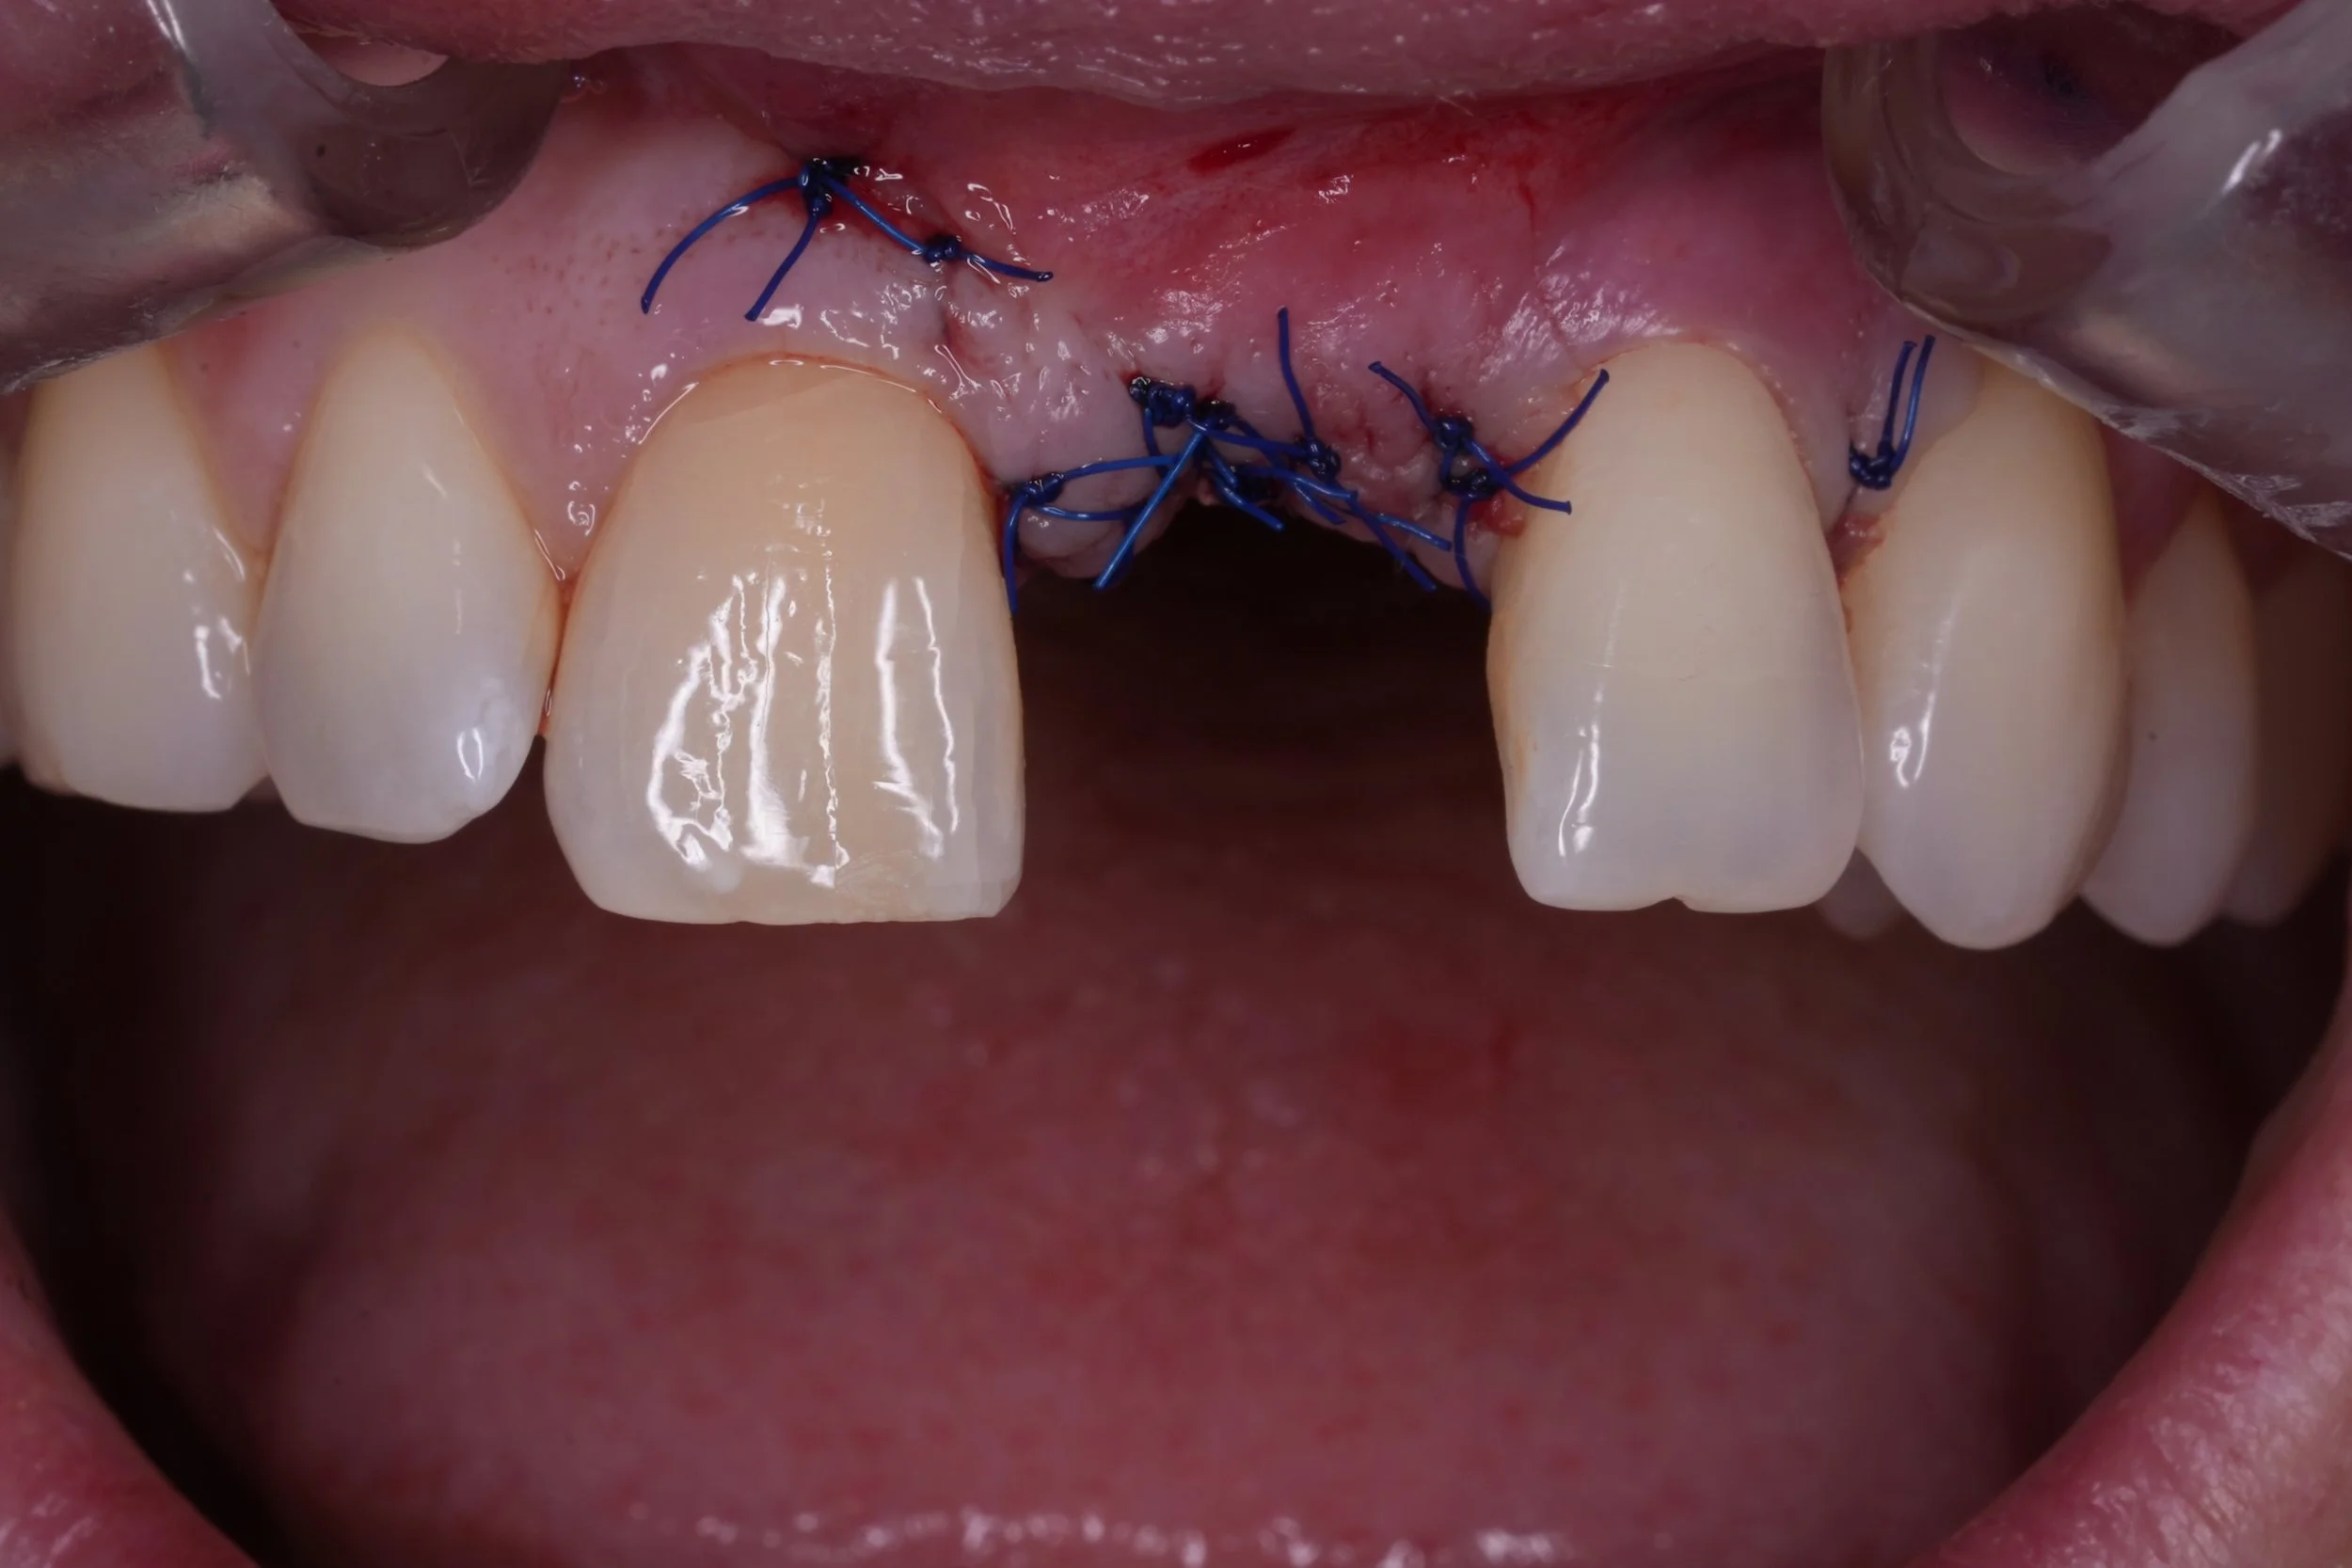

Dental Implants